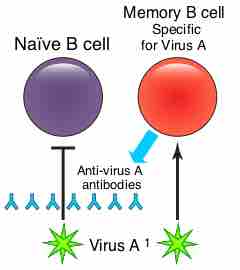

Memory B cells are a B cell sub-type that are formed following primary infection.

Naturally acquired active immunity occurs when a person is exposed to a live pathogen, develops the disease, and then develops immunity.